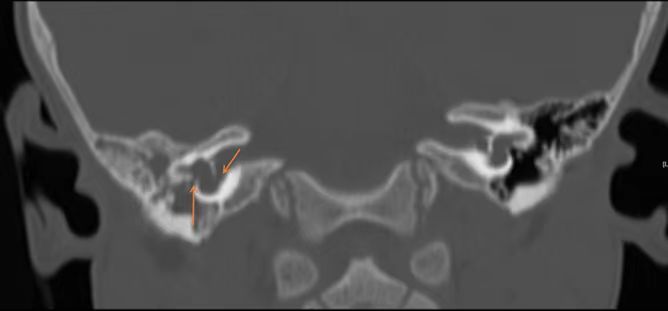

北京清华长庚医院耳鼻咽喉头颈外科副主任伊海金介绍,脑脊液耳漏是指脑脊液在颅内外压力梯度的作用下,从硬脑膜缺口及其所覆盖的颅骨缺损处经鼻腔、外耳道或开放伤口漏出的现象。这种“鼻涕”和普通鼻涕还不太一样,不粘稠,无色,更像清水。检查显示,患儿患有先天性内耳结构发育异常,不仅几乎无听力,言语发育受到影响,而且畸形的内耳与颅底相通,导致脑脊液自颅脑流入内耳、中耳、咽鼓管流到鼻腔,造成反复的鼻腔水样涕,过程中还导致感染,引发脑膜炎、吸入性肺炎等严重疾病。

经多学科讨论,在耳鼻咽喉头颈外科主任叶京英的指导下,伊海金主刀,陈雯婧主治医师为助手配合,为患儿实施全麻显微镜下脑脊液耳漏修补术,用腹部脂肪修补缺损的颅底。经术后抗炎、换药等对症治疗,患儿已摆脱了“流涕”的困扰。人工耳蜗植入是部分内耳畸形患者改善听觉的方式,在与家长充分沟通后,选择分期为患儿行人工耳蜗植入术,目前患儿已康复出院。